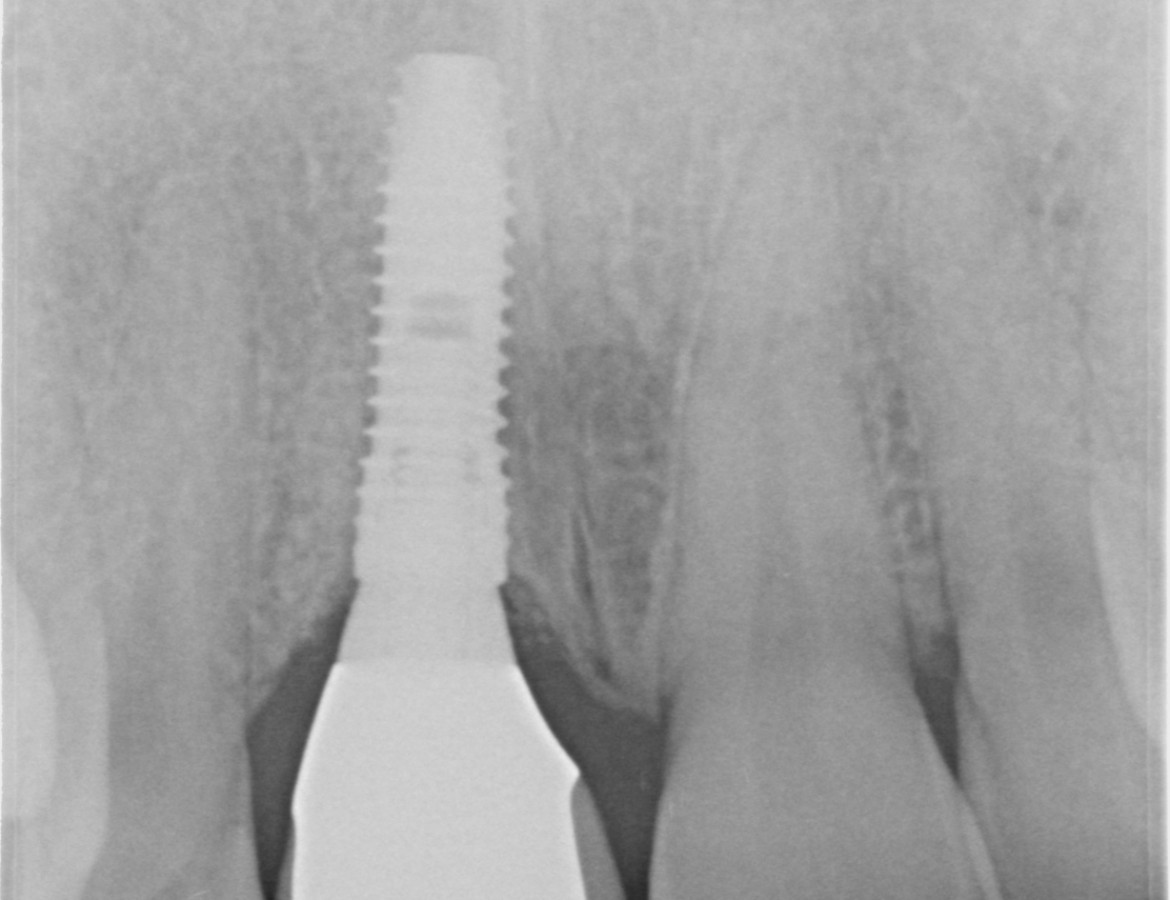

Pan Vincíř je herec. Mnoho let měl zlomenou pravou horní jedničku. Dlouho byla pevná, nebolestivá. Období lockdownu jsme využili k okamžitému zavedení zubního implantátu ihned po vytažení poškozeného zubu. Po třech měsících provizorní fáze jsme společně se zubním technikem vyrobili plně individualizovanou keramickou korunku. Všimněte si zejména krásnou, netknutou dáseň v okolí implantátu a korunky.

- Keramická korunka na implantátu